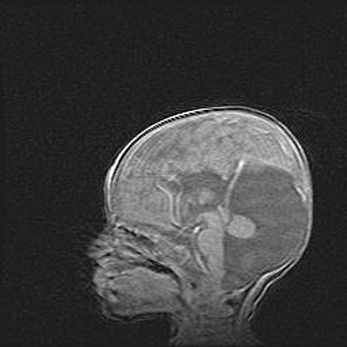

Мальформация Денди-Уокера. Киста задней черепной ямки.

Агенезия мозолистого тела.

Возраст: 2,5 месяца

Вес: 2420 г

Пол: женский

Окружность головы: 37 см

Срок гестации: 32 недели

Мальформация Денди—Уокера — редкий вид патологии ЦНС, представляющий собой врожденный порок развития каудального отдела ствола и червя мозжечка, ведущий к неполному раскрытию срединной (Мажанди) и латеральных (Лушка) апертур IV желудочка мозга. Для этогно синдрома характерна триада симптомов: гипотрофия червя мозжечка и/или полушарий мозжечка, кисты задней черепной ямки, гидроцефалия различной степени. В 70% случаев порок сочетается и с другими аномалиями головного мозга, в частности с агенезией мозолистого тела.